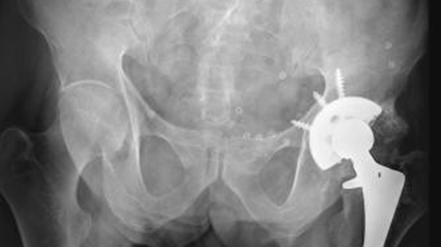

Fig 147. Artropatía reumática.

A: Rx AP. Disminución simétrica del espacio articular derecho, con osteopenia y sin presencia de osteofitos. En el lado izquierdo se colocó prótesis bipolar, por los severos cambios articulares.